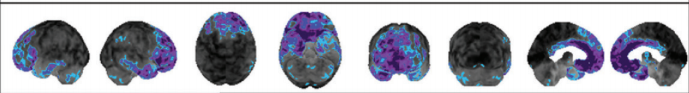

Alzheimer disease